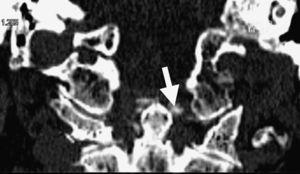

La afectación del esqueleto axial por condrocalcinosis ha estado asociada a depósitos cálcicos en disco intervertebral, ligamento amarillo, articulaciones facetarias e incluso articulaciones sacroilíacas. La calcificación del ligamento transverso del atlas (figs. 1-3) es una manifestación menos frecuente y se ha denominado síndrome de Crown Dens; constituye un cuadro clínico asintomático en la mayoría de las ocasiones, pero también puede estar asociado con brotes agudos de dolor cervical, rigidez y fiebre con las connotaciones de dificultad diagnóstica añadidas en estos casos.

En los estudios radiológicos realizados destaca la aparición de una espondiloartrosis cervical y calcificaciones en el ligamento transverso del atlas y ligamentos alares a nivel de la articulación atlo-axoidea (fig. 4).

El síndrome de Crowned Dens fue descrito por primera vez en 1985 por Bouvet et al1,2. El diagnóstico se basa en la asociación de un cuadro clínico compatible y unos hallazgos en las pruebas de imagen, fundamentalmente depósitos cálcicos en ligamentos de la articulación atlo-axoidea, visibles en la TC3,4.